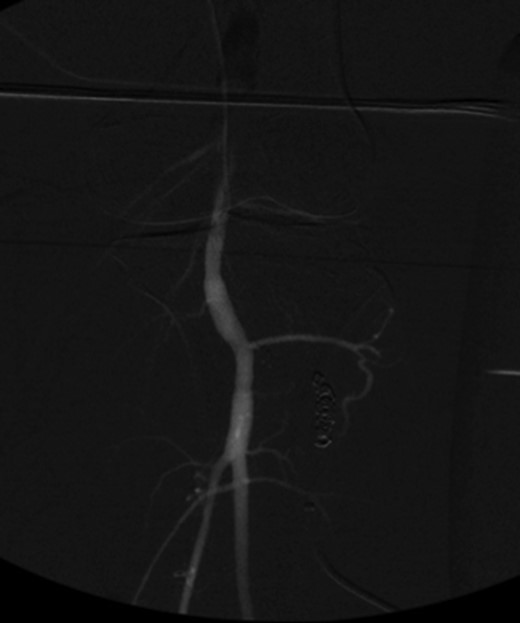

Patient underwent a left lower extremity angiogram. During the procedure she was found to have patent aorta and bilateral common iliac artery. There was no disease visualized in the left external iliac artery, common femoral artery (CFA), SFA, patent previously placed stent, patent above and below the knee PA and two vessel run off to the foot (Fig. 1). Upon delayed fluoroscopic images we identified contrast filling the deep venous system rather quickly suggesting a high volume fistula (Fig. 2). We then identified the fistula between ATA and ATV. Although ATA was previously ligated there was retrograde filling of the artery from unnamed branches, which communicated with the venous system as shown in. In the midcalf (ATA) was cannulated with a micropuncture needle. Micropuncture wire was inserted and a 5-Fr sheath was inserted after exchanging over wire. At this point VortX coils (Boston Scientific) were placed from the curve of ATA until the whole AVF was sealed. Anterograde angiogram showed no flow through the fistula (Figs 3 and 4). There was a palpable PT and DP pulse at the completion of the procedure. Sheath was removed, pressure dressing applied. Patient was discharged home same day. Recovery has been unremarkable. Three months follow-up claudication symptoms have significantly improved.

Anterograde angiogram showed no flow through the fistula tract with two vessels run off.